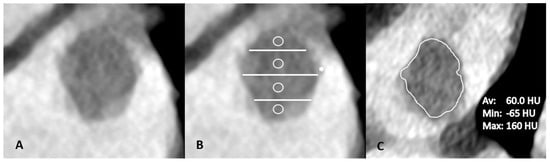

2.4. Imaging Analysis